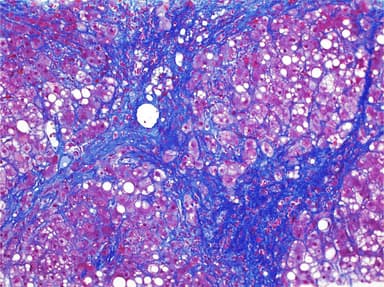

FISH: Liposarcoma

Interpretation of Liver Biopsies

Modern approach to liver pathology including fatty liver disease, hepatitis, and cirrhosis.